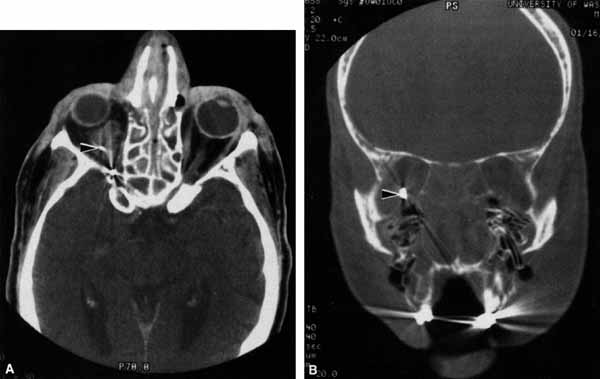

Fig. 19 A. A patient underwent endoscopic exploration of the right ethmoid and maxillary sinus for persistent epistaxis. Postoperatively the patient demonstrates right proptosis, restricted extraocular movements of the right eye, and a dilated right pupil. Instillation of 0.1% pilocarpine resulted in miosis on the right and no change on the left. Computed tomography (CT) shows a vessel clip lateral to the optic nerve (arrow), near the position of the ciliary ganglion. B. Coronal CT scan showing the clip lateral to the optic nerve (arrow).

Damage to parasympathetic fibers proximal to the ciliary ganglion also results in a dilated pupil but without the susceptibility to 0.1% pilocarpine. Trauma, surgery, inflammation, and intracranial aneurysms may produce a dilated pupil. Damage to the parasympathetics proximal to the ciliary ganglion is usually associated with ptosis and third cranial nerve ophthalmoplegia.